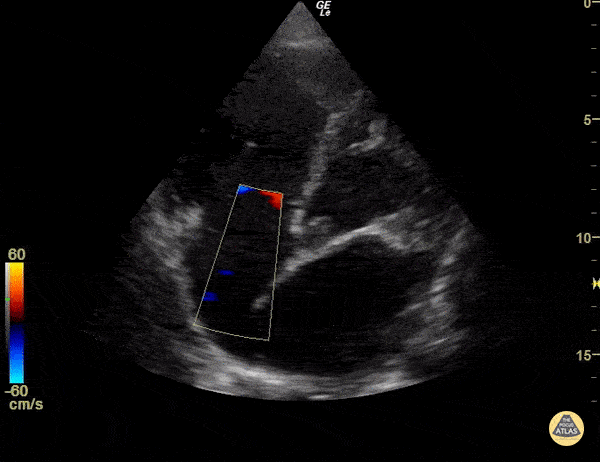

Insuffisance tricuspide fonctionnelle dans l’EP aiguë

En embolie pulmonaire aiguë, la surcharge brutale de pression dans l’artère pulmonaire entraîne une dilatation aiguë du VD.

Cette dilatation provoque fréquemment une insuffisance tricuspide fonctionnelle (IT) par élargissement de l’anneau tricuspide, entrainant une mauvaise fermeture des feuillets.

Flux d'insuffisance tricuspide au Doppler couleur. POCUS Atlas — © Reproduction éducative.